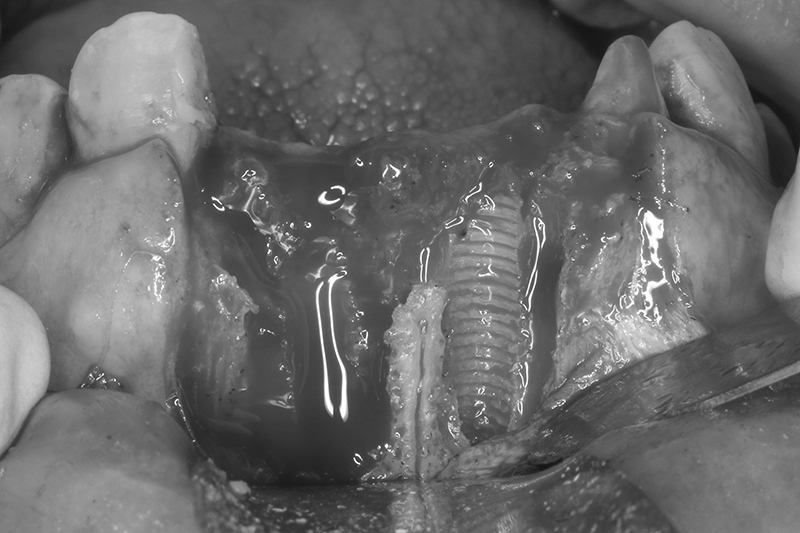

可見植體移除後骨缺損範圍大

明顯看到水平骨頭缺損範圍

垂直骨頭缺損情況